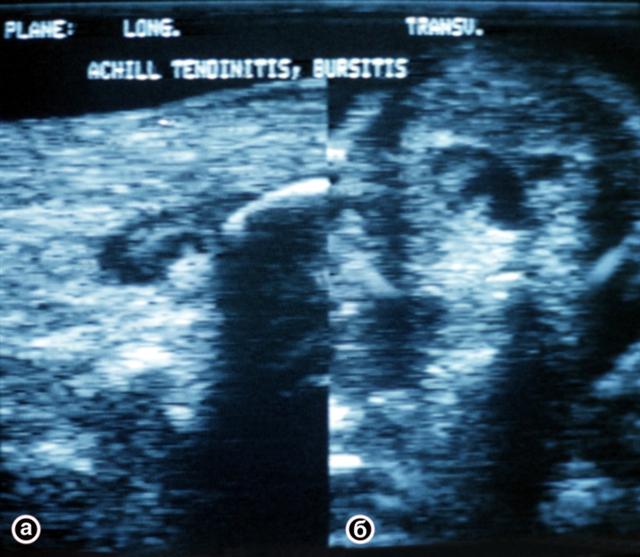

Рис. 2. Ультрасонограммы пяточного (ахиллова) сухожилия (а — продольный; б — поперечный срезы): в толще сухожилия видна обширная зона сниженной эхогенности, обусловленная кистой.